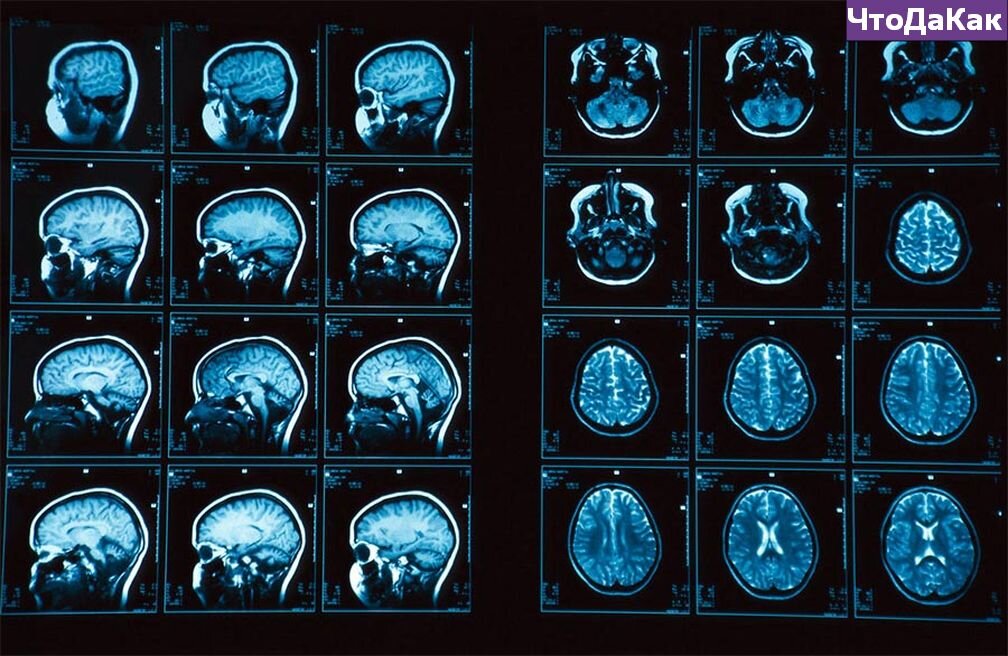

Исследования активности мозга с помощью томографии

Ученые изучили данные, полученные в ходе исследования симптомов разбитого сердца у 104 людьми, средний возраст которых составлял около 67 лет. Все эти материалы собирались с 2005 по 2019 года, на основе анализов и осмотров, проведенных с помощью компьютерной и позитронно-эмиссионной томографии. Большинство пациентов проходят данную процедуру для обнаружения раковых клеток, однако она также проводится для исследования активности клеток крови в костном мозге.

Исследователи наблюдали за пациентами на протяжении 2,5 лет после проведения томографии, что позволило им найти 41 человека с развивающимся синдромом разбитого сердца. Специалисты обнаружили, что по первичным результатам сканирования все участвовавшие в исследовании люди имели высокую «миндалевидную активность» мозга, вызванную сильным стрессом.

Согласно наблюдениям специалистов, люди у которых в последствии развивался синдром разбитого сердца, во время исследования имели на 15% больше активности в миндалевидном теле. И, как следствие, спустя год после исследования у них стало прогрессировать это заболевание. Другие же пациенты «заработали» синдром только через несколько лет после сканирования томографией. Эти результаты подтверждают прямую связь сердца и мозга.